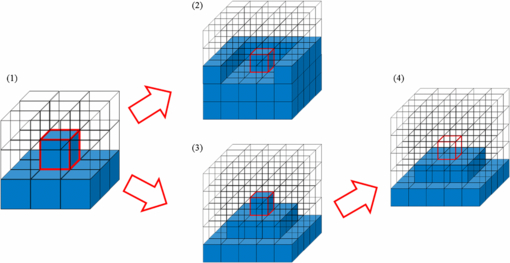

After determining the voxel resolution, the masses of the individual organs and tissues were also adjusted to the reference Korean data. In the development of the HDRK-Man, the organs and tissues had been adjusted on 2D slice images using Photoshop 7.0TM's Inner Grow and Outer Grow functions. Due to the fact that the boundary voxels were only changed in the transversal direction, some organs (e.g. the spleen) were significantly deformed in appearance. In order to avoid this problem, in the present study, a 3D volume adjustment program was developed for boundary voxel change in 3D space. Checking the smoothness of an organ surface around a boundary voxel, the program decides boundary voxels to be changed (as shown in figures 3 and 4) in order to make an organ shape as smooth as possible. Conflicts such as organ overlap could be detected by the program and resolved manually. The program not only obviated a great amount of repetitive work, but also enabled closer matching of organ and tissue masses to the reference Korean data.

Figure 3. Procedures for decreasing an organ volume in the 3D volume adjustment program.